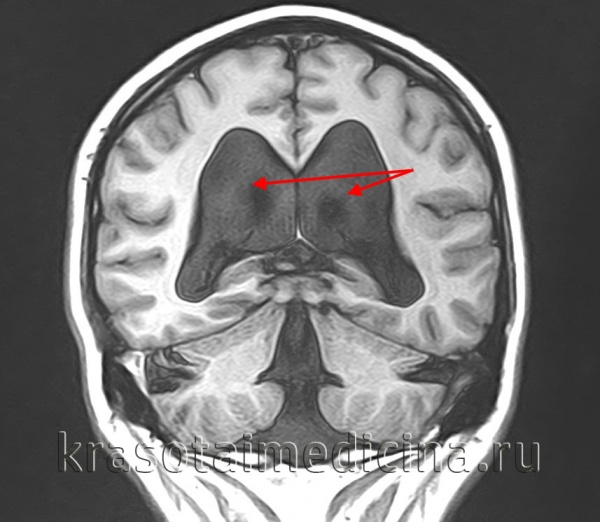

а - КТ: многокамерная гидроцефалия с признаками трансэпендимального отека.

б - Сагиттальное Т2-взвешенное изображение: стеноз водопровода с тривентрикулярной дилатацией. А, Б. КТ (А): внутрижелудочковое кровоизлияние с дилатацией желудочка. МРТ в Т2-режиме.